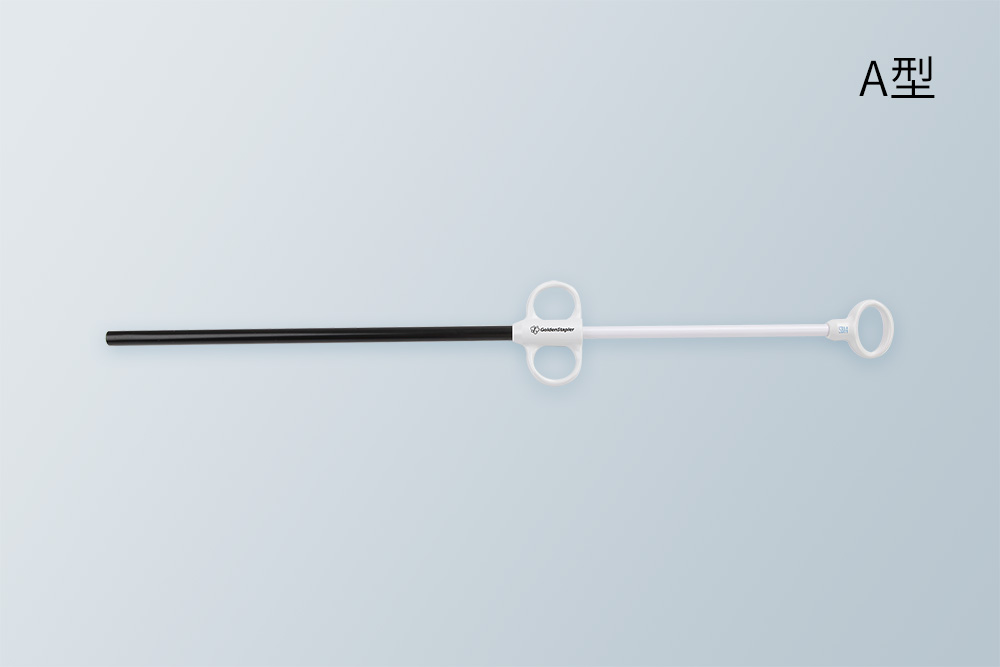

健瑞宝标本取出袋可用于胸或腹腔镜手术中,在胸或腹腔内盛装切除的标本并将此标本取出。产品采用柔软超强材质,抗爆破压高,防止漏液。有两种不同款式,按需选用,灵活方便。产品有多种规格及尺寸,适合于手术切除的不同尺寸标本。

健瑞宝标本取出袋可用于胸或腹腔镜手术中,在胸或腹腔内盛装切除的标本并将此标本取出。产品采用柔软超强材质,抗爆破压高,防止漏液。有两种不同款式,按需选用,灵活方便。产品有多种规格及尺寸,适合于手术切除的不同尺寸标本。

● 柔软环形钢丝设计,自动张口,以便装入标本

● 随意放入胸腔或腹腔,取标本方便

柔软钢丝袋口 柔软环形钢丝设计,自动张口,以便装入标本

灵活方便 随意放入胸腔或腹腔,取标本方便